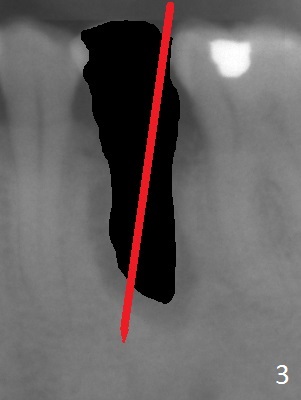

A 53-year-old man (probably bruxer, long roots) has 3 missing teeth (Fig.1 #14,18,29) and 1 fractured tooth (Fig.2 #20).  The fractue is associated with deep buccal pockets.  The buccal plate is most likely defective.  After extraction (Metronidazole), start osteotomy lingual and mesial (Fig.3 red long arrow) to reduce damage to the Mental Loop (Fig.4 red dashed line).  Damage to the Incisive Canal (yellow dashed line, the continuum of the Inferior Alveolar Canal after giving off the Mental Loop) is less significant.  Since the defect is long, use the longest implant and place it deep.  A long abutment (7 mm, green) with 5 mm cuff (pink) is required.  To have sufficient buccal gap for bone graft and probably membrane, the smallest two-piece implant is necessary (3.8 mm).